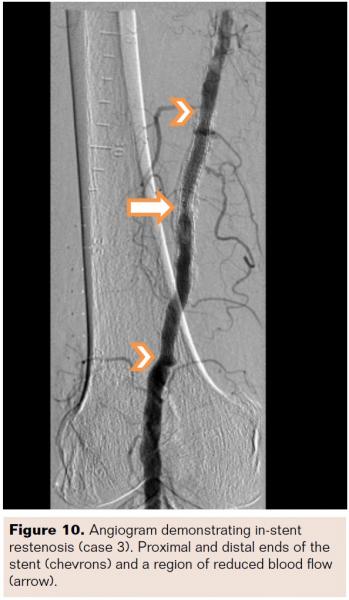

An 80-year-old black male with a history of hypertension, hyperlipidemia, and diabetes noted severe claudication in his right leg (Rutherford Class III; TASC A; ABI 0.86). The patient received a stent in the SFA 16 months prior. Angiography revealed reduced flow through the stented segment. Core laboratory adjudication measured 61% diameter stenosis, with a reference vessel diameter of 5.96 mm and a minimum lesion diameter of 2.32 mm (Figure 10). The lesion length was 29 mm within a 110 mm stent. Mild calcification was observed as well as a class 2 stent fracture (Figure 11). In the presence of a stent fracture, caution must be exercised since fractures increase the risk of suboptimal guidewire placement by sandwiching the guidewire between the stent and the vessel wall. Multiple angiographic views should be utilized to ensure proper guidewire placement. Stent fractures may impede the advancement of treatment devices, which may prolong procedure time and increase risk for vessel trauma, stent damage, and device damage. Stent fractures may also rupture PTA balloons, reducing treatment effectiveness and contributing to additional treatment time and cost.